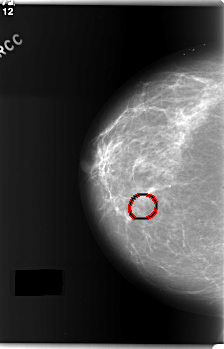

C_0169_1.RIGHT_CC

RIGHT_CC LINES 5920 PIXELS_PER_LINE 3800 BITS_PER_PIXEL 12 RESOLUTION 50 OVERLAY

FILE: C_0169_1.RIGHT_CC.OVERLAY

TOTAL_ABNORMALITIES 1

ABNORMALITY 1

LESION_TYPE CALCIFICATION TYPE AMORPHOUS DISTRIBUTION CLUSTERED

ASSESSMENT 4

SUBTLETY 2

PATHOLOGY MALIGNANT

TOTAL_OUTLINES 1

BOUNDARY